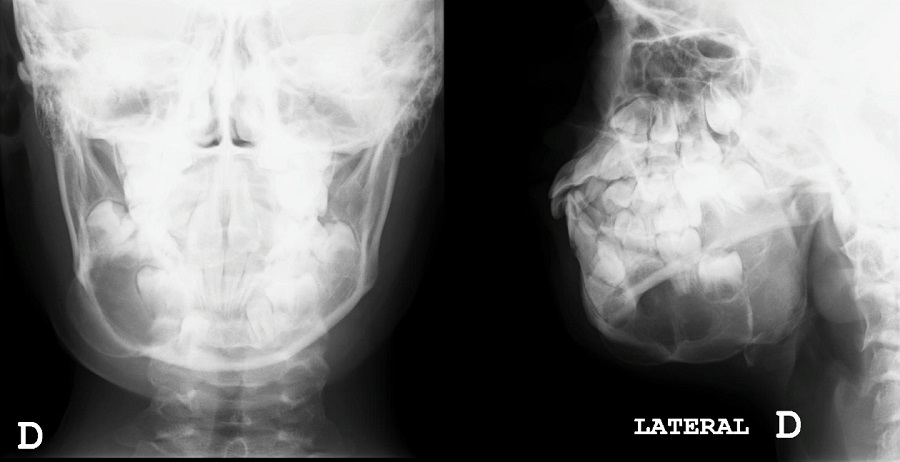

Paciente de 9 años que acude a consulta por bulto en zona mandibular de 2 meses de evolución, de consistencia dura, sin dolor ni inflamación asociada, ni infecciones previas. En ecografía clínica realizada en nuestro centro se objetiva lesión que produce protrusión de la cortical del hueso maxilar inferior, sin adherirse a tejidos blandos y con captación de Doppler de forma periférica. En la radiografía (Figura 1) solicitada posteriormente, se visualiza lesión lítica en rama derecha mandibular, expansiva, sin clara interrupción de la cortical que mide 3,6 cm, siendo sugestiva de benignidad. Con estos datos se deriva al paciente a Urgencias para valoración por Cirugía Maxilofacial, que amplía el estudio con analítica sanguínea, TAC (Figura 2) y ortopantomografía (Figura 3). Tras los resultados de las pruebas complementarias, entre los posibles diagnósticos diferenciales se encuentra el fibroma osificante de mandíbula. Se procede a su resección completa quirúrgica con buenos resultados y con biopsia que confirma el diagnóstico de fibroma osificante con focos sugestivos de quiste óseo aneurismático secundario. En el TAC de control se visualiza hueso inmaduro que ha ido ocupando la zona del defecto, sin evidenciarse recidiva.

Figura 1. Radiografía anteroposterior y lateral